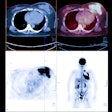

Overall efficacy:

PET/CT has been shown to be significantly more accurate (86%) in tumor staging compared to CT alone (63%) [235]. The results of a large number of studies has shown that the results of FDG PET imaging can have a major impact on oncologic patient management. Up to 15% of patients without clinical suspicion of recurrence or residual disease are found to have active tumor on PET imaging [47]. PET exam findings can change planned radiation therapy (dose, volume, or intent) in 27% of patients [47]. PET imaging can also detect unexpected sites of secondary malignancy (in 1.2 to 2% of patients) [75,113]. The identification of unexpected hypermetabolic foci on FDG PET imaging should prompt further evaluation as up to 71% of these foci can be malignant or premalignant [75]. Unfortunately, not all tumors will shown significant metabolic activity on FDG PET imaging [47]. PET exams are positive for tumor in about three-quarters of patients with known primary or residual tumor [47].

One other drawback of PET imaging is the underestimation of metabolic activity in tumors that are smaller than two times the spatial resolution of the scanner (partial volume effect) [6,118]. For a spherical lesion with a diameter 1.5 times the spatial resolution of the PET scanner at full width at half maximum, the measured maximum activity concentration is only 60% of the true activity (and the measured mean activity concentration on 30% of the true activity) [118]. Despite this limitation, using modern PET scanners, objects that measure as small as 5 mm can be visualized [1]. Assessment for malignancy and metastatic disease with PET FDG imaging is improved when supplemented by CT images [2]. PET imaging can also identify a more accessible tumor site for biopsy.